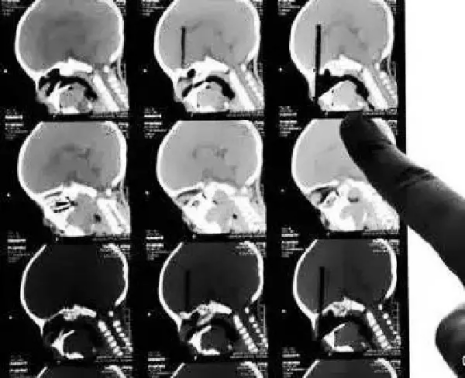

CT

CT的檢查原理是X光會斷層穿過人體,通過電腦計(jì)算后處理為二次成像。

優(yōu)點(diǎn):可以斷層看,經(jīng)后處理可以顯示更多信息。

缺點(diǎn):費(fèi)用比X光攝影貴,且CT檢查的輻射劑量通常高于單次X光攝影。

(筷子插入小朋友眼球的CT三維重建片)